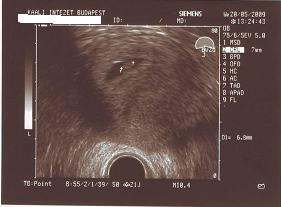

Jaj de lüke vagyok, a blogon nem is néztem, de már pótoltam, gyönyörűűűűűűűűű